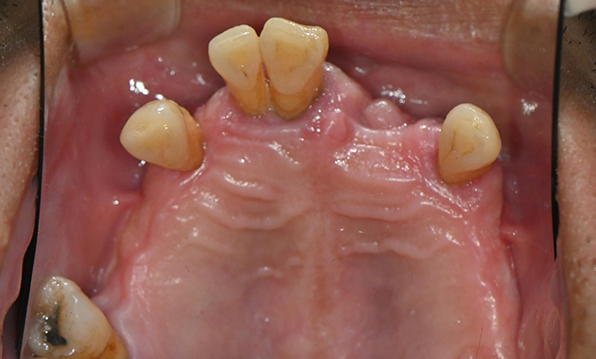

Case 02

Before After